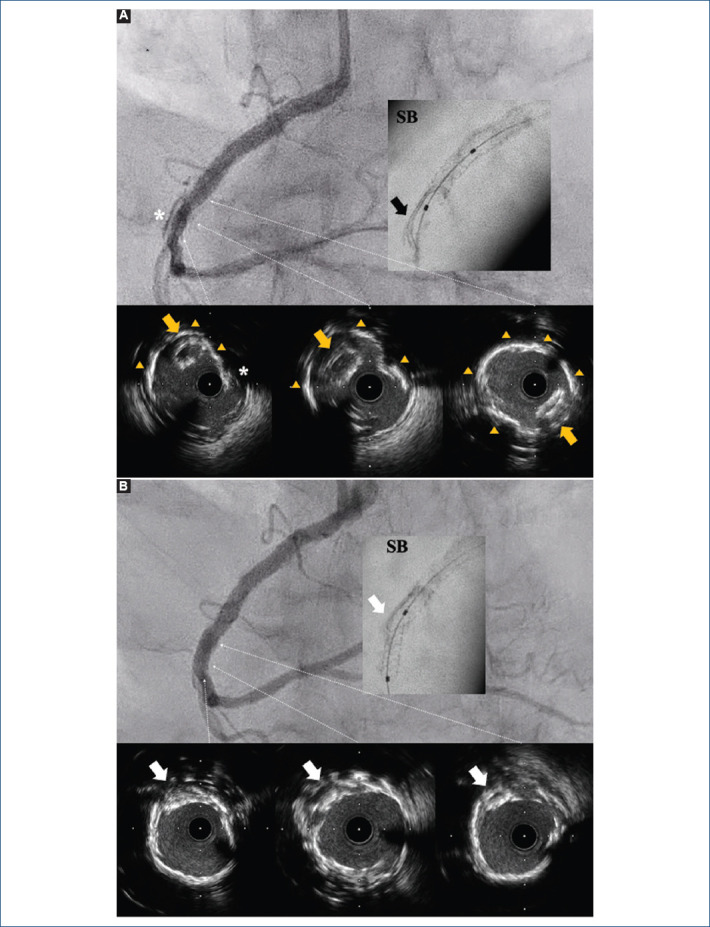

[Dislodged coronary stent: unexpectedly lost and found].

{"title":"[Dislodged coronary stent: unexpectedly lost and found].","authors":"Kristian Rivera, Gemma Mateus-Porta, Diego Fernández-Rodríguez, Luis R Puglla-Sánchez","doi":"10.24875/ACM.24000071","DOIUrl":null,"url":null,"abstract":"","PeriodicalId":93885,"journal":{"name":"Archivos de cardiologia de Mexico","volume":" ","pages":""},"PeriodicalIF":0.0000,"publicationDate":"2025-01-20","publicationTypes":"Journal Article","fieldsOfStudy":null,"isOpenAccess":false,"openAccessPdf":"https://www.ncbi.nlm.nih.gov/pmc/articles/PMC12058099/pdf/","citationCount":"0","resultStr":null,"platform":"Semanticscholar","paperid":null,"PeriodicalName":"Archivos de cardiologia de Mexico","FirstCategoryId":"1085","ListUrlMain":"https://doi.org/10.24875/ACM.24000071","RegionNum":0,"RegionCategory":null,"ArticlePicture":[],"TitleCN":null,"AbstractTextCN":null,"PMCID":null,"EPubDate":"","PubModel":"","JCR":"","JCRName":"","Score":null,"Total":0}